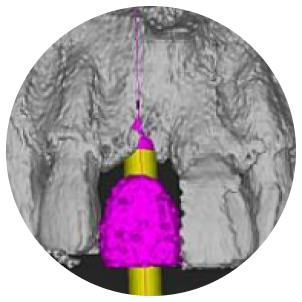

当院では、CT撮影による3D画像診断をもとに、骨の厚みや高さ、密度を立体的に把握。必要があれば、骨造成を取り入れたインプラント治療計画をご提案しています。